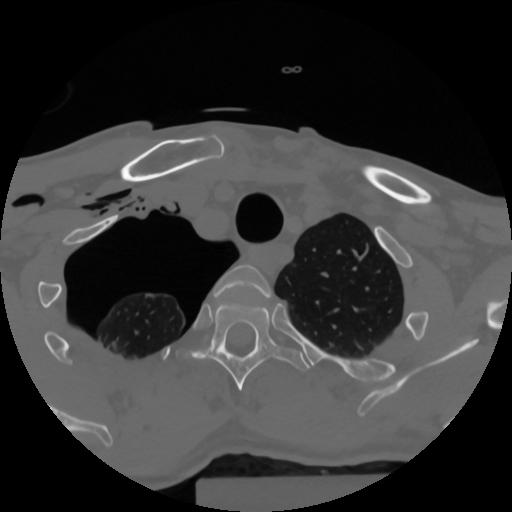

12 P.BLANDAS,,Vol,0.5,P.BLANDAS,,